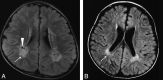

Fig 4.

Type 4. Delayed myelination. T1WI (A) and T2WI (B) of a 4-month-old patient (case 26) with an ATRX mutation in exon 35 (c.7156C>T, p.Arg2386Stop). Myelination appears only at the posterior limb of the internal capsule (long arrow) on T1WI. At 4 months of age in a healthy infant, high intensity should extend from the junction of the anterior limb of the internal capsule at the callosal genu (short arrow) all the way back to the visual cortex (arrowhead) along the internal capsule and optic radiations.